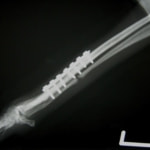

トイプードル 右遠位橈尺骨短斜骨折のALPSによる内固定

当院ではAdvanced Locking plate system(ALPS)と、Locking compression plate system(LCPS)という骨接合法で骨折症例の治療を行っています。

Advanced Locking Plate System

従来型のプレートのように広い面積で骨と接するプレートを用いて固定を行った場合、プレート下の骨はプレートとの接触面において血行が絶たれ壊死し、それがリモデリングされると骨密度が低下する。この骨密度の低下防ぐために、骨折部局所への血行を温存することの重要性が近年改めて認識されるようになってきている。Advaed Locking Plate System (ALPS)は従来型のプレートシステムの欠点を改良し、より使いやすく、より骨への血行を阻害しないようにというコンセプトで作られた。